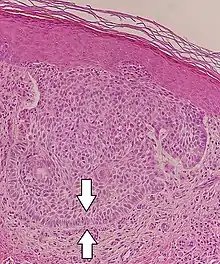

| Squamous-cell carcinoma of the skin | Squamous-cell carcinoma of the skin is generally distinguishable by for example relatively more cytoplasm, horn cyst formation and absence of palisading and cleft formations. Yet, a high prevalence means a relatively high incidence of borderline cases, such as basal-cell carcinoma with squamous cell metaplasia (H&E stain at left in image). BerEP4 staining helps in such cases, staining only basal-cell carcinoma cells (right in image). | ![]() |